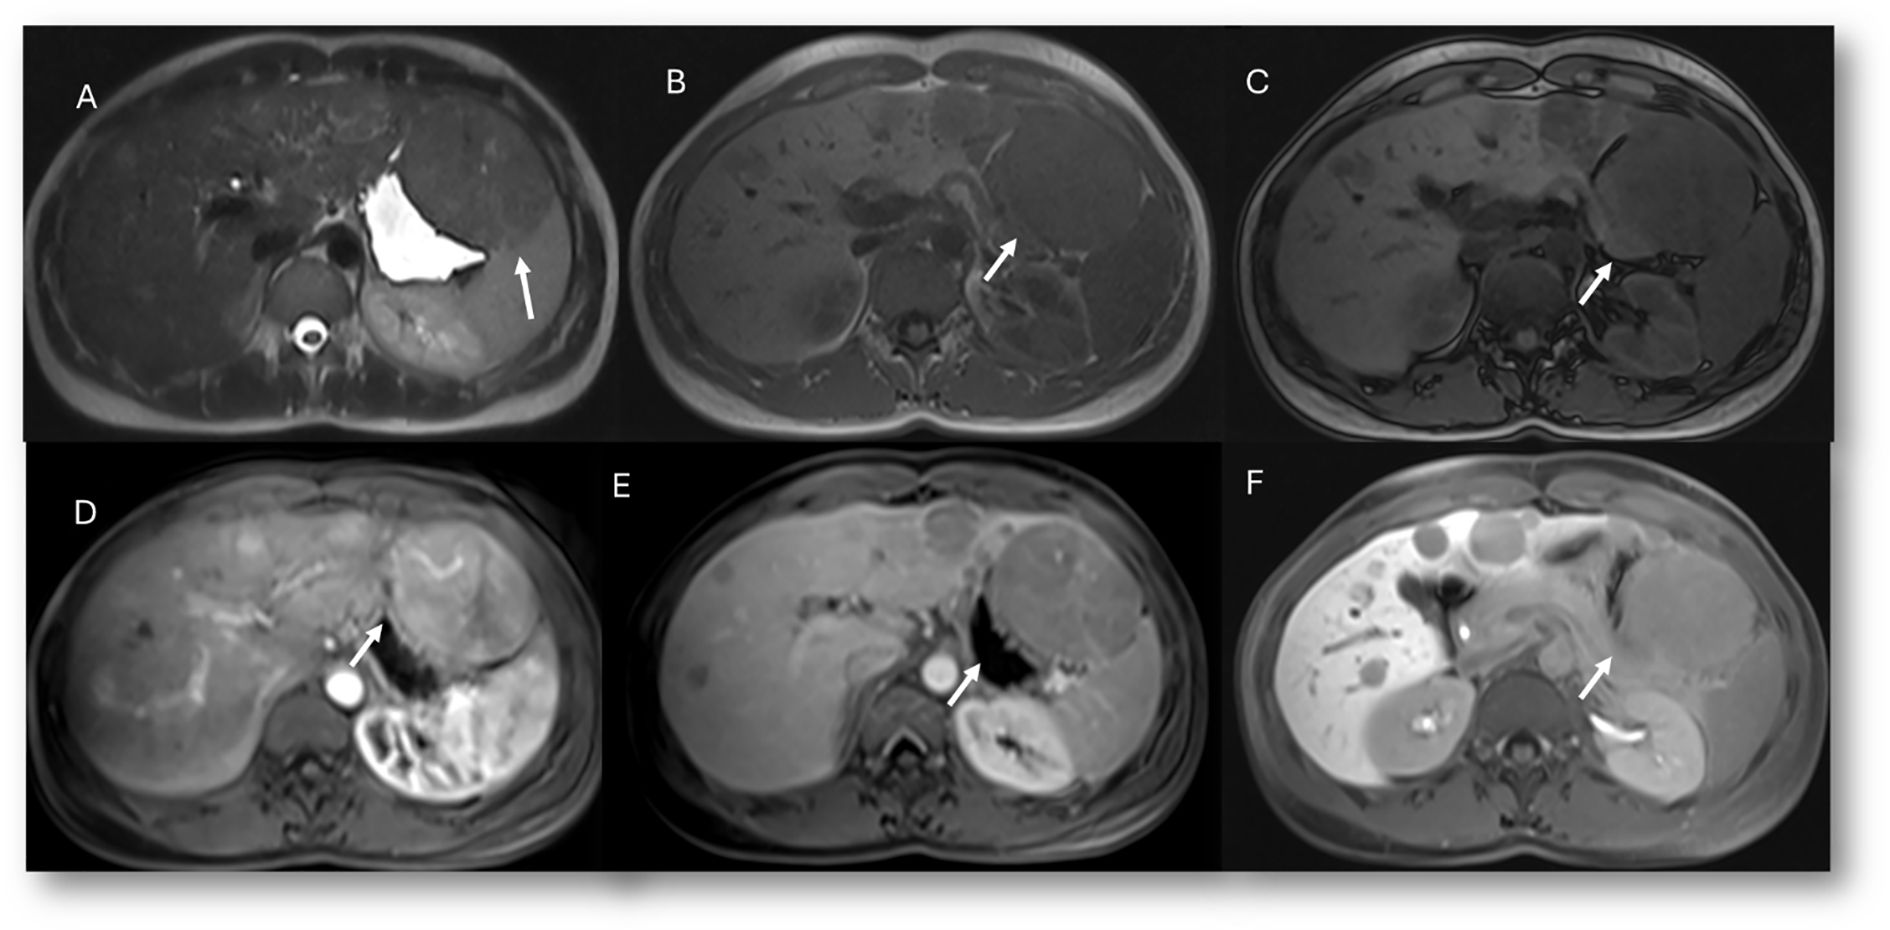

The established clinical indications for contrast-specific agents include characterization of focal lesions, detection and treatment planning for liver metastases, assessment of living liver donors (vascular and biliary anatomy and graft liver volume) or liver transplant complications, and study of bile leaks (94). With regard to characterization, it must be clear that hypointensity in the hepatobiliary phase is due to the lack of expression of OATP1B3, the principal contrast transporter. This pattern can be seen in both benign and malignant lesions such as hemangiomas and metastases, which is why hepatospecific contrast is not indicated when the diagnostic question is the differential diagnosis between these two lesions. In addition, diffuse uptake of contrast agent may be seen in focal nodular hyperplasia (FNH) and in FNH-like lesions, in liver parenchyma spared in steatosis patients, in some subtypes of adenomas (those with β-catenin activation), and in well-differentiated HCC (94). Since most adenomas do not show contrast retention, hepatospecific agents are suggested in the differential diagnosis between adenoma (Figure 7) and FNH lesions (Figure 8). Lastly, but of equal importance, is the fact that some lesions may present enhancement limited to the central portion due to retention of contrast by fibrous stroma, as in cholangiocarcinoma or in several types of liver metastases (95). In these conditions, it appears evident that lesion evaluation must necessarily be comprehensive and multiparametric, and not based only on the contrast pattern in the hepatospecific phase. However, bilirubin level evaluation remains mandatory, as hyperbilirubinemia can alter the results, and the MRI examination may not be diagnostic, since OATP1B3 is the principal contrast transporter, with optimal values being <6–8 mg/dl (96).

Figure 7. MRI assessment of FNH lesion (arrows) with Gd-EOB-DTPA contrast. In (A) (in-phase) and (B) (out-phase), the lesion shows hypointense signal with central scar and steatosis of the liver parenchyma in (B). In C (T2-W FS sequence), the lesion is hyperintense with central scar. During contrast study, the lesion shows non-rim hyperenhancement during arterial phase (D), no washout during portal (E) or transitional (F) phases, and hyperintense signal on hepatospecific phase (G).

Figure 8. MRI assessment of multiple adenoma lesions (arrows) with Gd-EOB-DTPA contrast. In (A) (T2-W sequence), lesions are hyperintense; in (B) (T1-W in-phase) and (C) (T1-W out-of-phase), lesions are hypointense. During contrast study, lesions show non-rim hyperenhancement during arterial phase (D), washout during portal phase (E), and hypointense signal on hepatospecific phase (F).